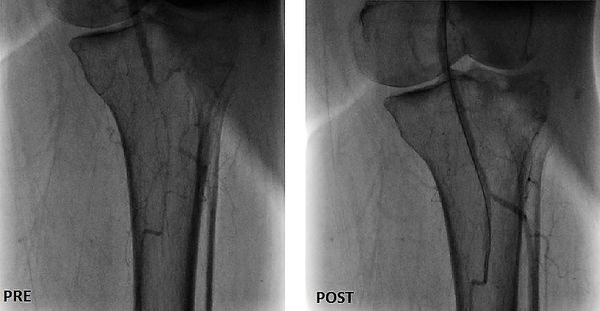

جراح أوعية دموية متخصص في علاج الوحمات الدموية للأطفال - انسداد الشرايين - قدم السكري والغرغرينا -علاج دوالي الساقين بالليزر

استشاري جراحة الأوعية الدموية و القسطرة التداخلية الطرفية